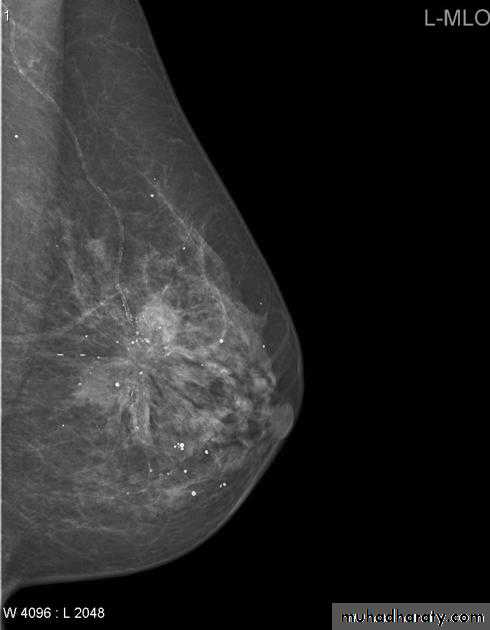

Infiltrating or invasive lobular carcinoma (ILC) of the breast is the second most common type of invasive breast cancer after invasive ductal carcinoma (IDC).

Radiographic features

ILC is more often multicentric and bilateral (10-15%). Therefore imaging evaluation of the contralateral breast is crucial. There can be very subtle changes such as progressive shrinkage or enlargement or reduced compressibility of the involved breast. Imaging often underestimates the disease.

Mammography

The sensitivity of mammography for the detection of ILC reportedly ranges between 55-80% 8. Because of the limitations of mammography in detecting ILC, other modalities, such as sonography and MR imaging, are being used in evaluating clinically suspicious findings and known cancers to assess the extent of disease. ILC are more commonly seen on the craniocaudal (CC), compared to the mediolateral oblique (MLO).

Invasive lobular CA